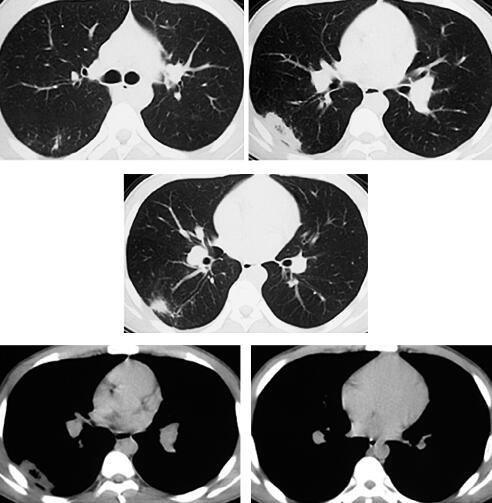

七、再问病史和检查

转入我院后详细询问病史得知:患者为高三学生,活动时间很少,虽坚持体育锻炼,但每天仍久坐10小时以上,且饮水少,经过“深挖”得知,本次发病前1个月患者曾有左下肢肿胀,自行好转,未诊治,之后一直有活动时气短,间断胸痛。因为于当地医院住院时的突出症状是寒战和高热,诊断为肺部感染,所以未问及此事。入院查体:体温36.6℃,心率74次/分,呼吸22次/分,血压140/80mmHg。神志清楚,问答合理,口唇无发绀,双肺呼吸音粗,未闻及干湿性啰音,心率74次/分,律齐,P2亢进,各瓣膜听诊区未闻及杂音,双下肢周径:髌骨上15cm:左46cm、右46cm;髌骨下10cm:左34cm、右33cm。至此真相大白,结合病史高度怀疑静脉血栓栓塞症。急查双下肢血管超声示:左侧腘静脉血栓形成;2013年3月14日CT肺动脉造影(CTPA)示:双侧肺动脉内多发充盈缺损影,以双侧肺门区为主(图4)。血D-二聚体3290μg/L。故患者明确诊断为静脉血栓栓塞症、肺血栓栓塞症、左侧腘静脉血栓形成、右下肺梗死合并感染。

图4